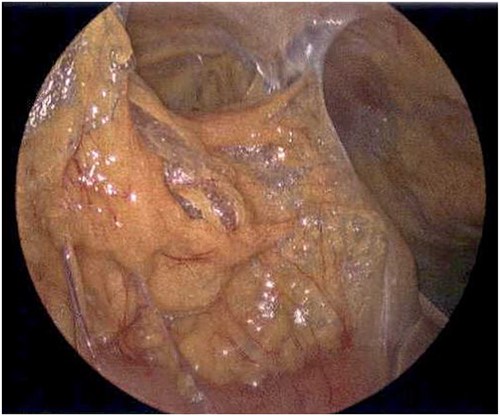

On Hospital Day 2, an interval CXR showed continued resolution of the right-sided pneumothorax but worsening subcutaneous emphysema of the bilateral chest wall and pneumoperitoneum (Fig. 3). Surgical consultation was sought, leading to diagnostic laparoscopy. In the abdomen, emphysematous changes within the gastrohepatic ligament and omental adhesions to the anterior abdominal wall were visualized (Figs 5 and 6). Laparoscopic exploration revealed no diaphragmatic injury or perforated viscera but identified emphysematous changes throughout the preperitoneal space, small and large bowel mesentery, and right paracolic gutter (Figs 7 and 8). Immediate post-op CXR no longer showed evidence of pneumoperitoneum (Fig. 4). The patient was transferred back to the ICU and extubated after three days on Day 5. After the removal of chest tube and transfer to a medical floor on Day 8, the patient developed aspiration pneumonia that was treated with antibiotics. She was discharged on Day 15.

Laparoscope revealing emphysematous changes within the gastrohepatic ligament.

Laparoscope of the large bowel revealing subserosal emphysema within the adventitia.